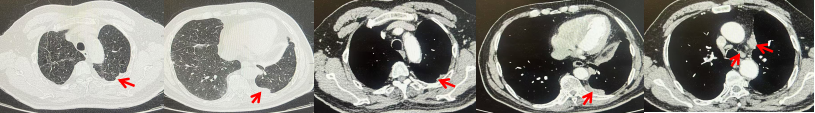

2024.11.19患者出现右侧胸痛,复查胸部CT检查示右侧胸膜肿物,大小约31mmX24mm,右侧4、5肋骨骨质破坏,考虑转移(如图2)。建议患者穿刺活检取病理明确诊断,患者拒绝,经MDT会诊后结合影像学表现及病史考虑为胸膜转移,肋骨转移,分期为rT0N0M1a IVA期,DFS仅仅17个月。2024.12.05起行信迪利单抗联合培美曲塞+卡铂方案治疗4周期,复查胸CT评效PR(如图3)。之后给予信迪利单抗+培美曲塞维持治疗6周期,期间复查CT评效PR(如图3)。目前信迪利单抗+培美曲塞维持治疗中,截止至目前PFS约为8个月,治疗期间未出现明显毒副反应。

图3:患者免疫联合化疗治疗后胸部CT,(A、B)图展示信迪利单抗联合培美曲塞+卡铂治疗

4周期(2025.02)疗效,(C、D)图展示信迪利单抗+培美曲塞维持治疗6周期(2025.07)疗效

2024.09.12复查胸部CT示左侧胸膜结节,大者约为27mmx13mm,考虑转移可能性大,纵隔淋巴结增大,恶性?(如图6)。患者行胸膜穿刺活检取病理,结果示(胸膜)结合免疫组化,支持鳞状细胞癌,PD-L1(克隆号28-8)TPS约20%。分期为rT0N2bM1a IVA期,DFS为10个月。2024.09.24起行替雷利珠单抗联合紫杉醇+卡铂方案治疗4周期,复查胸CT评效SD(如图7)。后患者因脑梗塞停止治疗,于综合医院就诊,后未返院复查及治疗。

图7:替雷利珠单抗联合白蛋白紫杉醇+卡铂治疗4周期后(2024.12)胸部CT肺窗及纵隔窗